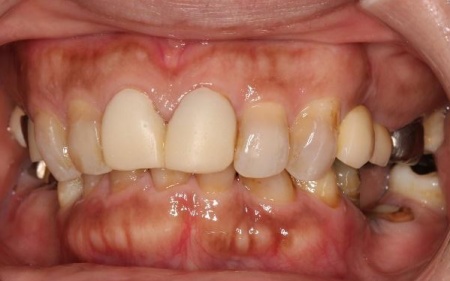

治療後

手術から3ヶ月後、下に仮の入れ歯を作製したあと、下の入れ歯とインプラントにマグネットを装着して固定し、上あごには保険の入れ歯を作製しました。

上下の入れ歯で問題なく噛めることを確認してから、下あごの最終的な入れ歯を作製し治療を終了しました。